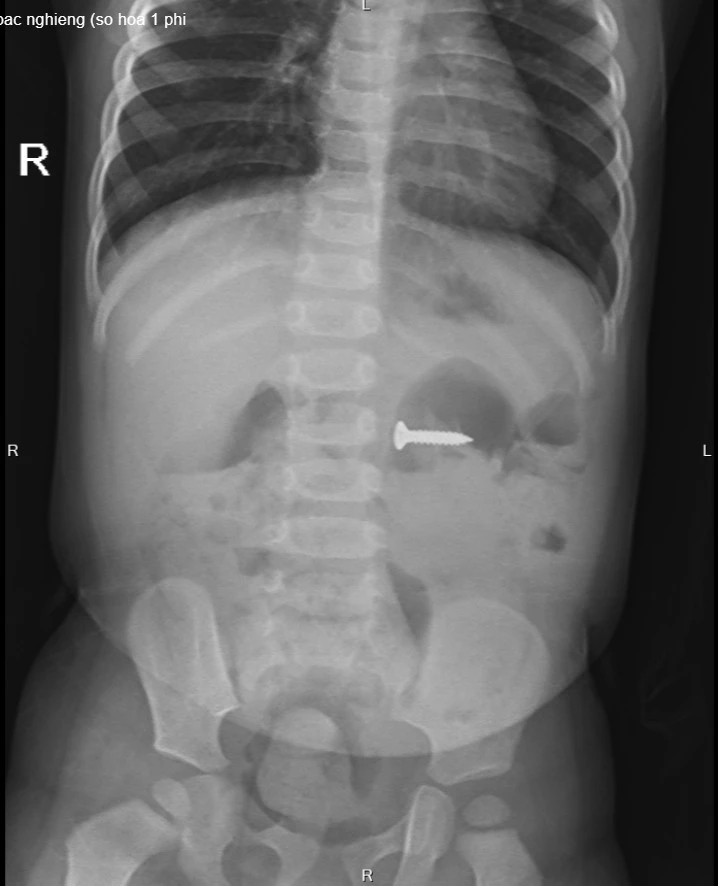

Tại Bệnh viện Sản nhi tỉnh Phú Thọ, các bác phát hiện dị vật đinh vít sắc nhọn kích thước 2 cm trong dạ dày. Với tính chất sắc nhọn, nếu không loại bỏ kịp thời, đinh vít có thể gây tổn thương đâm thủng thành ruột, dạ dày, thậm chí có thể gây tổn thương nhiều vị trí mà chiếc đinh đi qua.

Hình ảnh chụp XQ phát hiện đinh vít nhọn nằm trong dạ dày của trẻ.